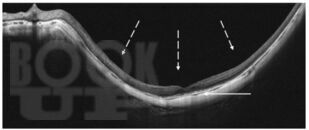

Учебное пособие содержит информацию о морфофункциональных изменениях органа зрения при нормальной беременности. Подробно описаны осложнения со стороны органа зрения на фоне патологической беременности. Приведён порядок ведения беременности и родов у женщин с заболеваниями глаз, а также при офтальмологических патологиях, связанных с развитием гестационных осложнений. Указаны изменения со стороны органа зрения, учитывающиеся при выборе способа родоразрешения.